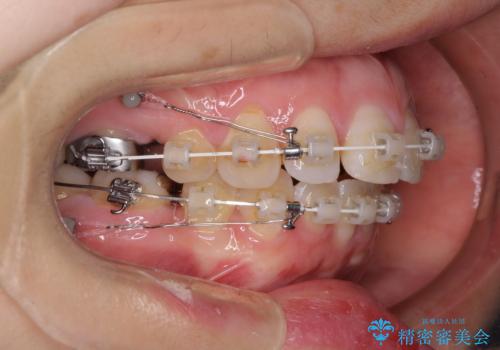

- 矯正装置

- 審美装置

上下正中を左右対称に揃えるため、アンカースクリューや補助装置を使用しながら口元を下げていくこととしました。